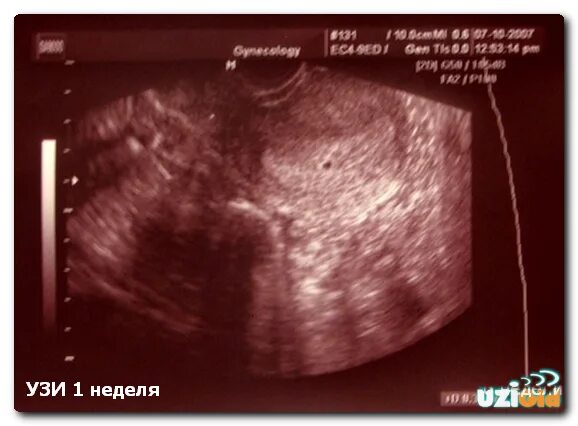

Беременна 2 недели срок